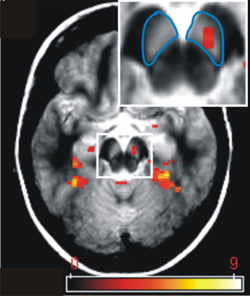

Foto:

FMRT-Aktivierung: Dargestellt ist die Aktivierung der Substantia nigra/ Area tegmentalis ventralis des Mittelhirns. Diese Region ist beteiligt an der Regulation von Motivation und Verarbeitung von Belohnungserwartung. Die Substantia nigra/ Area tegmentalis ventralis ist blau markiert und die mittels funktioneller Magnetresonanztomographie (fMRT) gemessene Aktivierung ist in rot dargestellt.